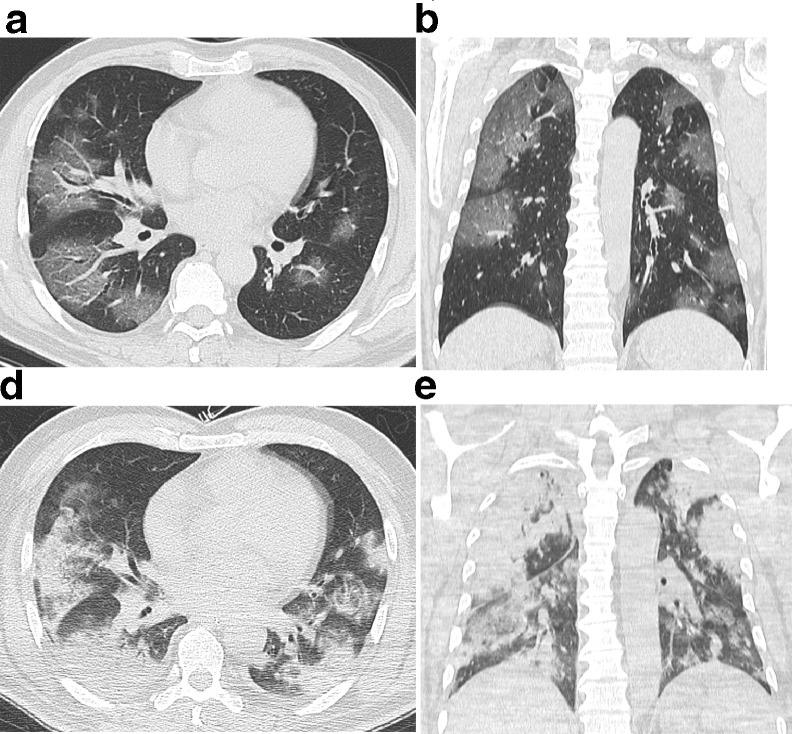

Fifty-three patients with confirmed COVID-19 infection underwent thin-section CT examination. Two chest radiologists independently evaluated the imaging in terms of distribution, ground-glass opacity (GGO), consolidation, air bronchogram, stripe, enlarged mediastinal lymph node, and pleural effusion.

Fourty-seven cases (88.7%) had findings of COVID-19 infection, and the other six (11.3%) were normal. Among the 47 cases, 78.7% involved both lungs, and 93.6% had peripheral infiltrates distributed along the subpleural area. All cases showed GGO, 59.6% of which were round and 40.4% patchy. Other imaging features included "crazy-paving pattern" (89.4%), consolidation (63.8%), and air bronchogram (76.6%). Air bronchograms were observed within GGO (61.7%) and consolidation (70.3%). Neither enlarged mediastinal lymph nodes nor pleural effusion were present. Thirty-three patients (62.3%) were followed an average interval of 6.2 ± 2.9 days. The lesions increased in 75.8% and resorbed in 24.2% of patients.

COVID-19 showed the pulmonary lesions in patients infected with COVID-19 were predominantly distributed peripherally in the subpleural area.